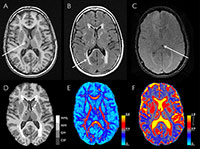

Participants in the study underwent brain MRI, which included the use of an advanced technique called diffusion tensor imaging (DTI), and blood testing to measure levels of N-terminal pro b-type natriuretic peptide (NT-proBNP), which is primarily used to help detect, diagnose and evaluate the severity of heart failure.

The researchers evaluated the brain MRI results for markers of early brain disease, including a loss of brain volume, microstructural changes and white matter lesions, which indicate areas of cells that have been damaged by injury or disease.

"Diffusion tensor imaging gives us information on the microstructural organization of the brain's white matter," Dr. Zonneveld said. "It is thought that microstructural brain changes precede brain changes, such as white matter lesions."

The results of DTI showed that participants with higher NT-proBNP levels had worse microstructural organization within the white matter. A statistical analysis revealed that higher NT-proBNP levels were also associated with smaller total brain volume and larger white matter lesion volume.

"The brain volume loss was predominantly in the gray matter," Dr. Zonneveld said.